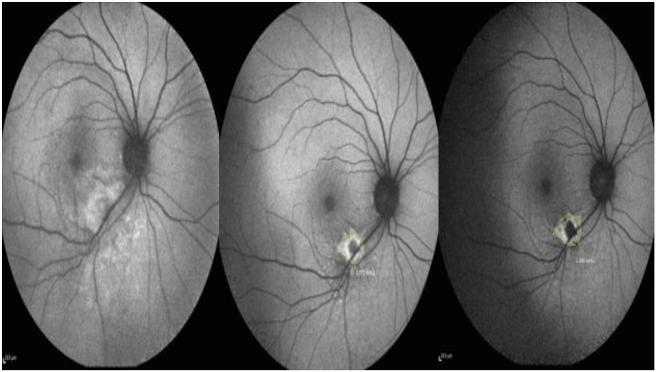

A randomized interventional comparative study was conducted on 14 patients with ocular toxoplasmosis who were treated with oral azithromycin and 13 patients who were treated with oral trimethoprim/sulfamethoxazole for 6-12 weeks. The achievement of treatment criteria in the two groups and lesion size reduction were considered as primary outcome measures.

The resolution of inflammatory activity, decrease in the size of retinochoroidal lesions, and final best corrected visual acuity (BCVA) did not differ between the two treatment groups. The lesion size declined significantly in all patients ( = 0.001). There was no significant difference in the reduction of the size of retinal lesions between the two treatment groups ( = 0.17). Within each group, there was a significant improvement in BCVA after treatment; BCVA increased by 0.24 logMAR in the azithromycin group ( = 0.001) and by 0.3 logMAR in the trimethoprim/sulfamethoxazole group ( = 0.001).

Drug efficacy in terms of reducing the size of retinal lesions and visual improvement was similar in a regimen of trimethoprim/sulfamethoxazole or azithromycin treatment. Therefore, if confirmed with further studies, therapy with azithromycin seems to be an acceptable alternative for the treatment of ocular toxoplasmosis.